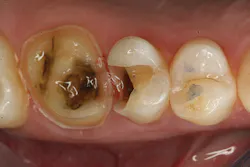

The clinical case in Figure 3 illustrates a patient who presented with a large, failing restoration containing cracks and decay. The patient was interested in an all-ceramic restoration. Occlusion was checked with articulating paper prior to treatment with a CAD/CAM restoration (figure 4). All previous restorative materials were removed from the tooth (figure 5). The tooth was restored using Grandio Core Dual Cure (Voco) build-up material (figure 6). A crown preparation was completed for a chairside CAD/CAM crown using the CEREC system (Dentsply-Sirona). The material of choice for this restoration was IPS e.max CAD (Ivoclar Vivadent), which is seen in Figure 7 after milling and in precrystallization form. The restoration was tried in and then polished, glazed, and placed in the oven for crystallization. The internal surface was then etched with 4.9% hydrofluoric acid, rinsed, and then coated with a silane coupler to create an optimal surface for bonding with the resin luting agent. The tooth was isolated and cleaned prior to etching. Once etched, the adhesive bonding agent (Futurabond U) was activated to mix the two liquids within the single-dose blister package. The blister seal was broken with the bonding agent brush and the adhesive was applied and agitated for 20 seconds. The adhesive was lightly dried for five seconds and then cured with an LED curing light for 10 seconds. A dual-cured adhesive resin luting agent (Bifix QM) was dispensed into the crown with its automix syringe (figure 8). The crown was seated and excess cement was removed after a two-second light cure. The tooth was then flossed and occlusion was checked (figure 9). The patient was very satisfied with the final result.

Figure 6: Teeth after restoration with Grandio Core Dual Cure build-up material (Voco)